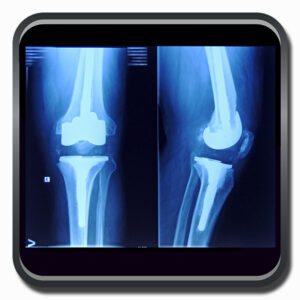

Algumas Cirurgias Complexas realizadas por profissionais da COFIB: